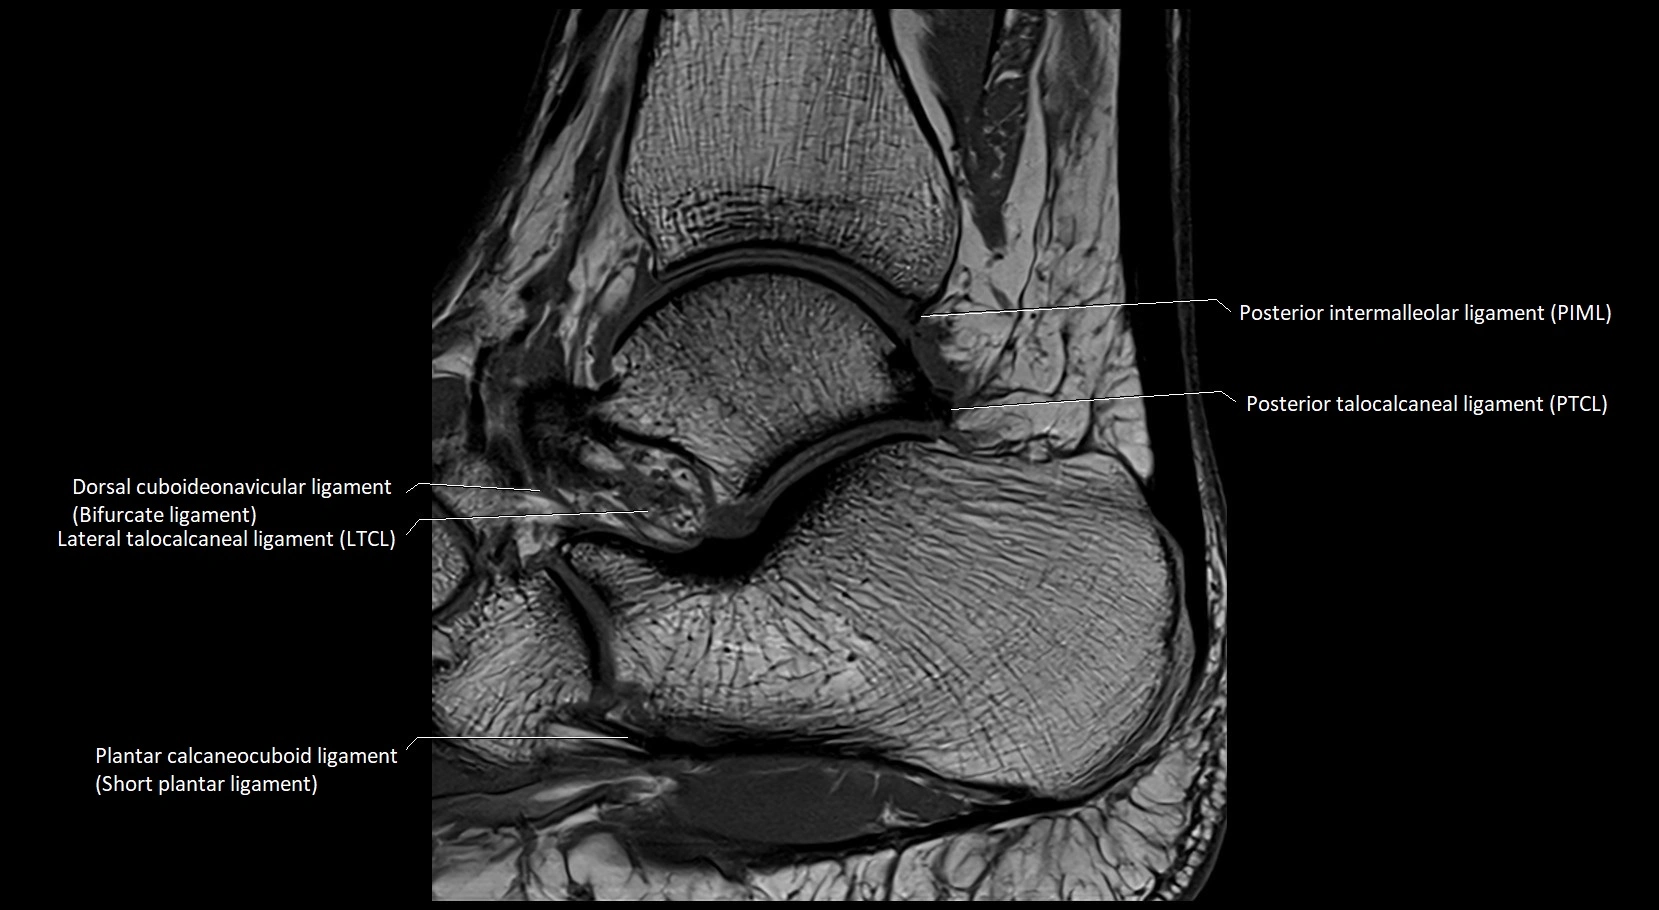

MRI image

image